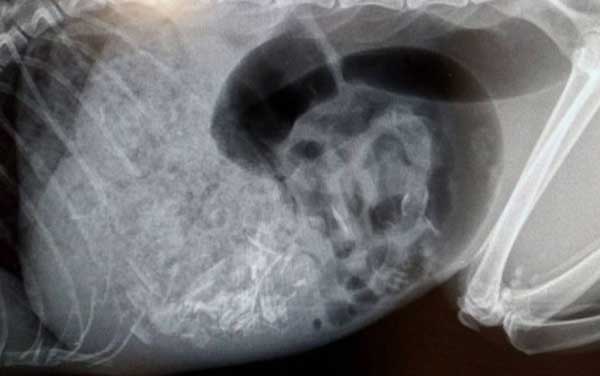

A veterinarian was summoned, who, after conducting an X-ray, discovered a small chip attached to Rosie's body. Additionally, a foreign organism was found intact in Rosie's stomach, prompting immediate action.

**A:** The X-ray revealed a rat of considerable size inside Rosie's stomach, causing it to swell unusually.